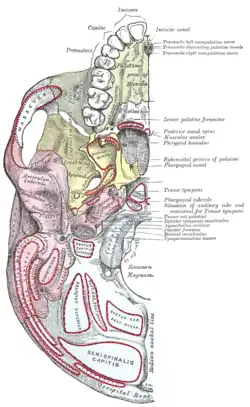

Left maxilla. Outer surface. Base of skull. Inferior surface.

Base of skull. Inferior surface.